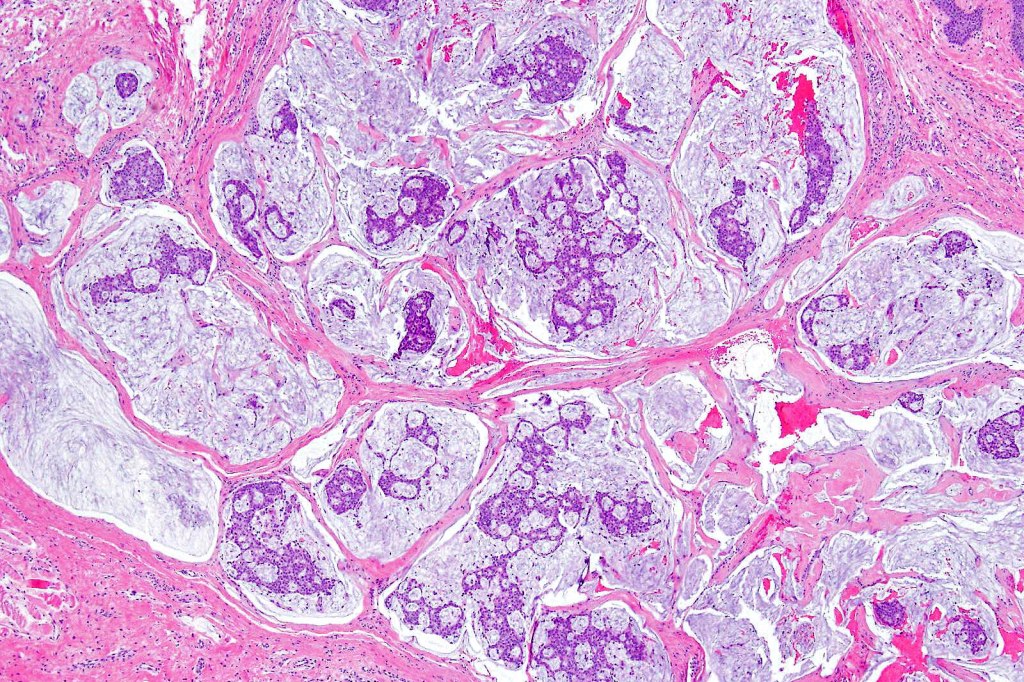

•Mucinous carcinoma is characterized by epithelial islands dispersed in a rich mucinous stroma

•DPAS, colloidal iron & Alcian blue ph 2.5 +ve

•EMPSGCa– multiple nodules of uniform epithelial cells with vesicular nuclei & small nucleoli

•Cyst formation sometimes evident

•Papillae & cribriform pattern sometimes evident

•+/- invasive mucinous carcinoma (50%)